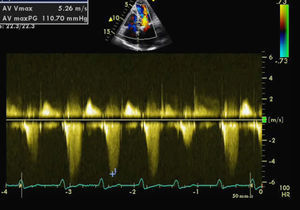

The patient was admitted for decompensated heart failure. Transthoracic echocardiography (TTE) performed on the first day of hospitalization (with HR 120–150bpm) (Figure 1) revealed aortic valve fibrosis with no restriction of opening, together with mild regurgitation.

The MV presented fibrocalcification, with increased echogenicity of the annulus; the anterior leaflet and subvalvular apparatus were obstructing the LVOT, resulting in an intraventricular gradient of 110mmHg and moderate paroxysmal regurgitation (probably related to the intermittent nature of the LVOT obstruction). The left atrium was severely dilated (6.1cm), and the left ventricle was hypertrophied (diastolic diameter 4.3cm) but with good global systolic function. The right chambers were of normal size, with pulmonary artery pressure estimated at 40mmHg.